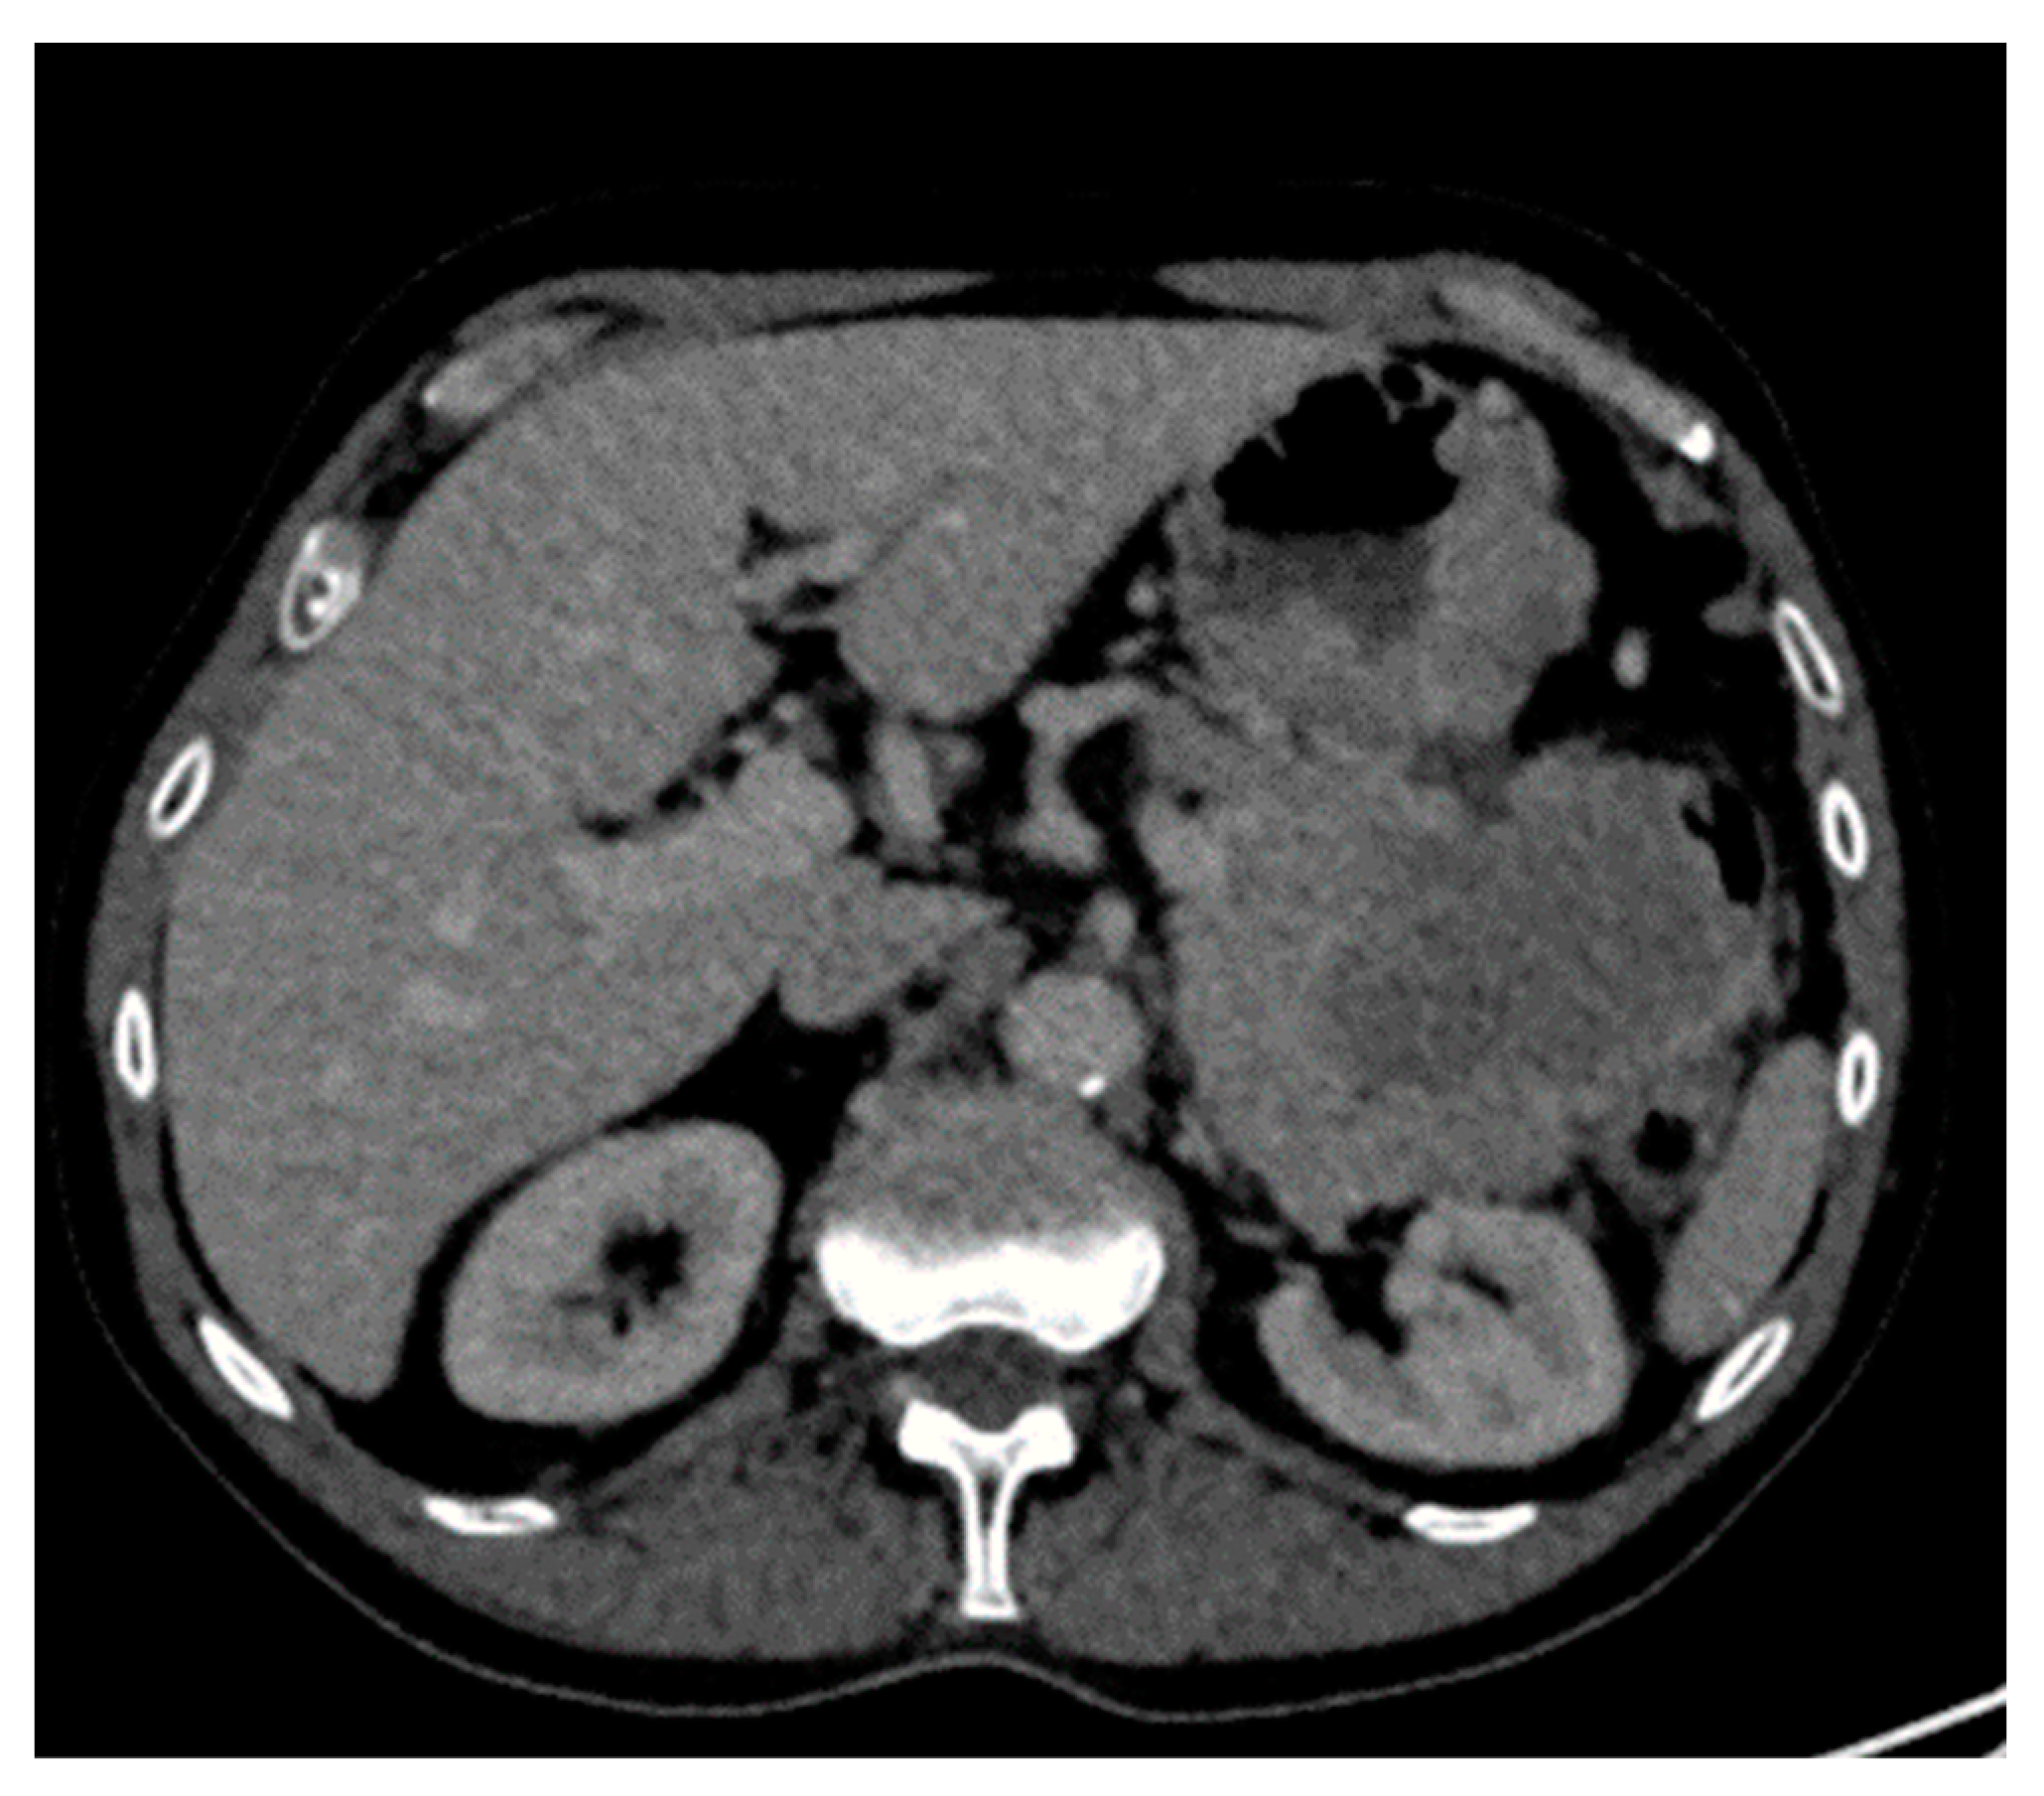

9. Renal

- Mei, Y.H.; Yu, J.P.; Li, G. An extramedullary plasmacytoma in the kidney of a 14-year-old girl: Case report and review of the literature. Medicine 2017, 96, e6092. [Google Scholar] [CrossRef] [PubMed]

- Spence, R.A.; Thwaini, A.; O’Rourke, D.M. Primary plasmacytoma of the kidney. Case Rep. Urol. 2013, 2013, 239580. [Google Scholar] [CrossRef]

- Zhang, S.Q.; Dong, P.; Zhang, Z.L.; Wu, S.; Guo, S.J.; Yao, K.; Li, Y.H.; Liu, Z.W.; Han, H.; Qin, Z.K.; et al. Renal plasmacytoma: Report of a rare case and review of the literature. Oncol. Lett. 2013, 5, 1839–1843. [Google Scholar] [CrossRef] [PubMed]